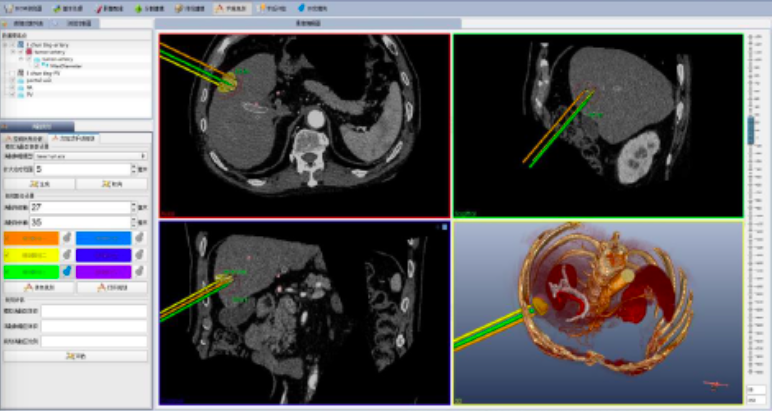

SUNYA自主研发的多模态影像三维融合引导介入手术导航系统,是以术中实时超声影像与CT、MR、PET等其他模态影像融合进行微波、射频、激光等介入手术导航。系统具有术前规划、术中器械定位导航和多模态医学影像融合显示、以及术后评估功能。

术前手术规划功能——影像三维分析

直观显示三维形态(肿瘤、管道、器官)

定量分析肿瘤参数(体积、最大径)

精确确定空间位置(肿瘤距离管道、重要器官的距离)

适形匹配消融热场(布针、能量)